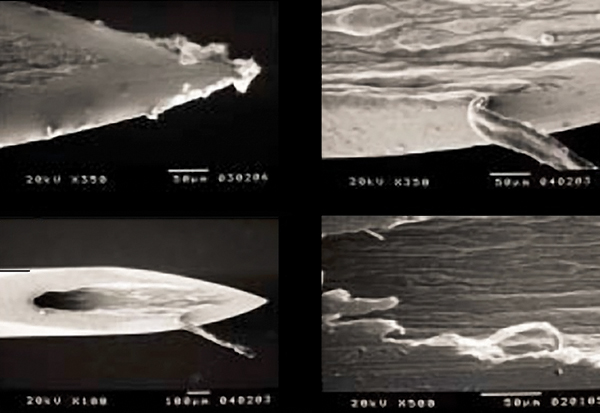

A needle with manufacturing defects is more likely to have existing, or easily created, barbing and splintering, which may result in issues with the penetration process of the needle, damage to soft and neuronal tissues, hemorrhage, or causing moderate to severe pain.34 During the manufacturing process, the cutting of the needle bevel can lead to irregularities in the stainless steel, which may result in these adverse outcomes (Figure 3). The creation of the irregularities is related to both the cutting process and the quality of steel being used.35

Microscopic view of irregularities of unused dental needles (from: Sanchez DE, Fernandez RE. Microscopic assessment of dental needles. Guadalajara University. Used with permission.)

Figure 3